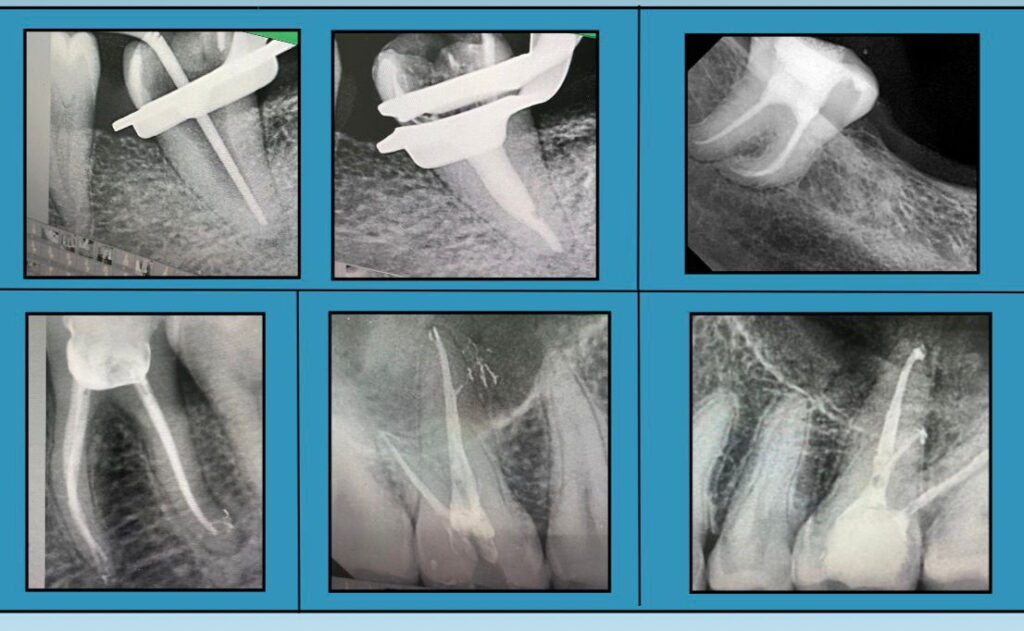

Dr. Neelanjana Majee is a highly skilled MDS specialist in Conservative Dentistry & Endodontics, offering expertise in advanced endodontic procedures and comprehensive dental care. With a strong clinical focus on precision, patient comfort, and long-term treatment success, she is proficient in performing single and multi-visit root canal treatments, re-treatments, and endodontic surgical procedures, including micro-endodontics.

✔ Single & Multi-Visit Root Canal Treatments ✔ Re-Treatments (Surgical & Non-Surgical) ✔ Endodontic Surgical Procedures ✔ Micro-Endodontics ✔ Esthetic Dentistry – Veneers, Anterior & Posterior Composites ✔ Prosthodontics – Crown Preparations, Endocrowns, FPDs, CD, RPD ✔ Biomimetic Restorative Dentistry ✔ Post & Core ✔ Simple & Surgical Extractions

Root Canal Treatment